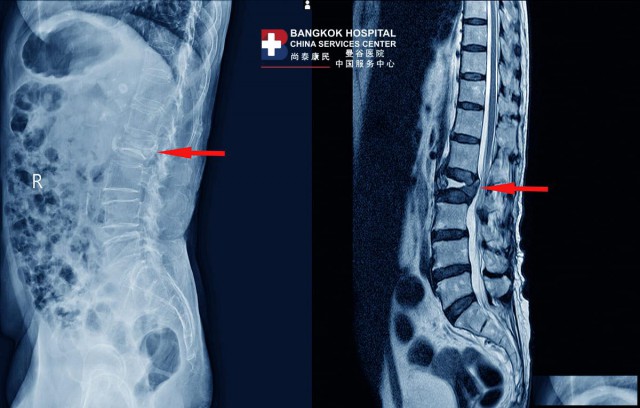

脊柱凹陷诊断

曼谷医院脊柱中心Chaidej Srasomboon博士表示,一般情况下,脊柱凹陷通常通过X线影像来诊断,但在某些患者中,X线影像无法清楚地显示凹陷的脊柱,可能需要MRI 扫描以协助进一步诊断。

另一个需要诊断的是骨质疏松症,尚泰康民——曼谷医院服务中心提醒需要通过骨矿物质密度( BMD)测试来诊断。